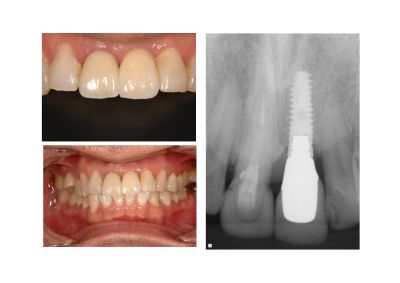

今回の症例では、重度の歯周病にかかった歯をできる限り保存し、矯正治療や歯周組織の再生治療を組み合わせながら、インプラントと天然歯が共存できる状態へ導いた流れを、非常に分かりやすく共有してくださいました。

また、歯周病をお持ちの方にインプラントを埋める際の注意点や、インプラント周囲炎を防ぐためのメインテナンスの重要性について、最新の論文を基に解説くださり、たいへん学びの多い時間となりました。